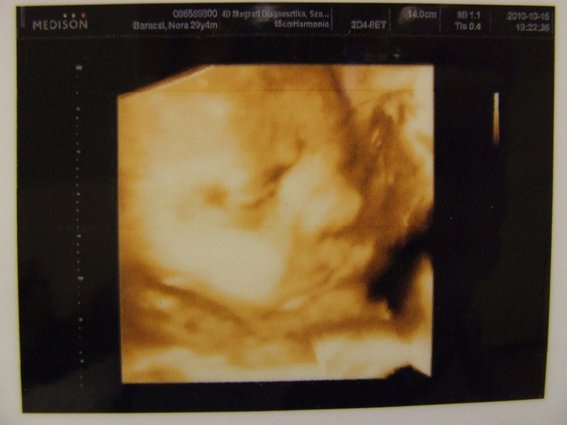

Bocsi, most kicsit rövid és önző leszek, most megyünk 4D-re!!! :)

Majd jövök fotókkal és olvasgatok is majd, mert úgy látom elég sok minden volt megint.